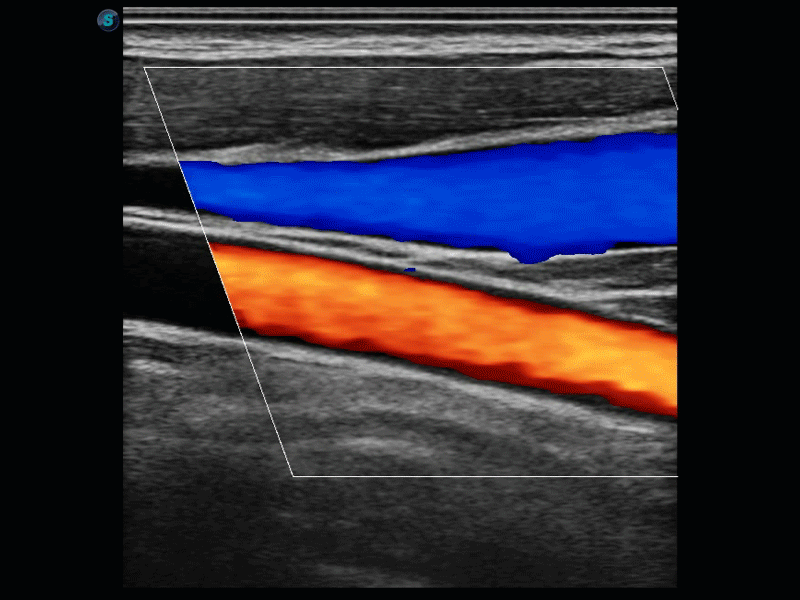

实时宽景成像技术

通过彩色血流和实时宽景相结合,可观察到完整的动静脉血流,方便医生检查。实时扫查过程中,如有任何操作失误也可以很容易地进行回扫擦除,而不会中断扫查。

临床图像